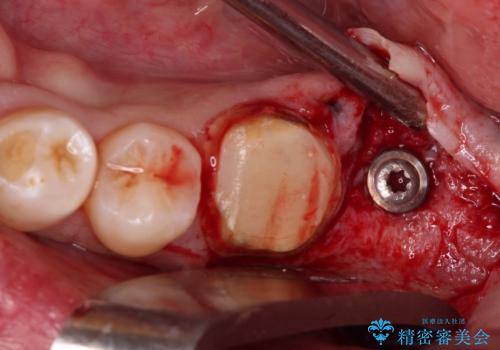

- 近医にて奥歯の抜歯が必要と言われたとのことで来院された患者様です。

診査の結果、歯が破折しており、抜歯が必要な状態でした。

最後方歯であるため、入れ歯かインプラントかどちらかの補綴治療を行うこととなりますが、ご希望によりインプラント補綴治療を行うこととしました。

インプラントにはストローマン社のSLActiveを使用し、埋入から補綴までおよそ3か月と、短期間で治療を進めることができました。